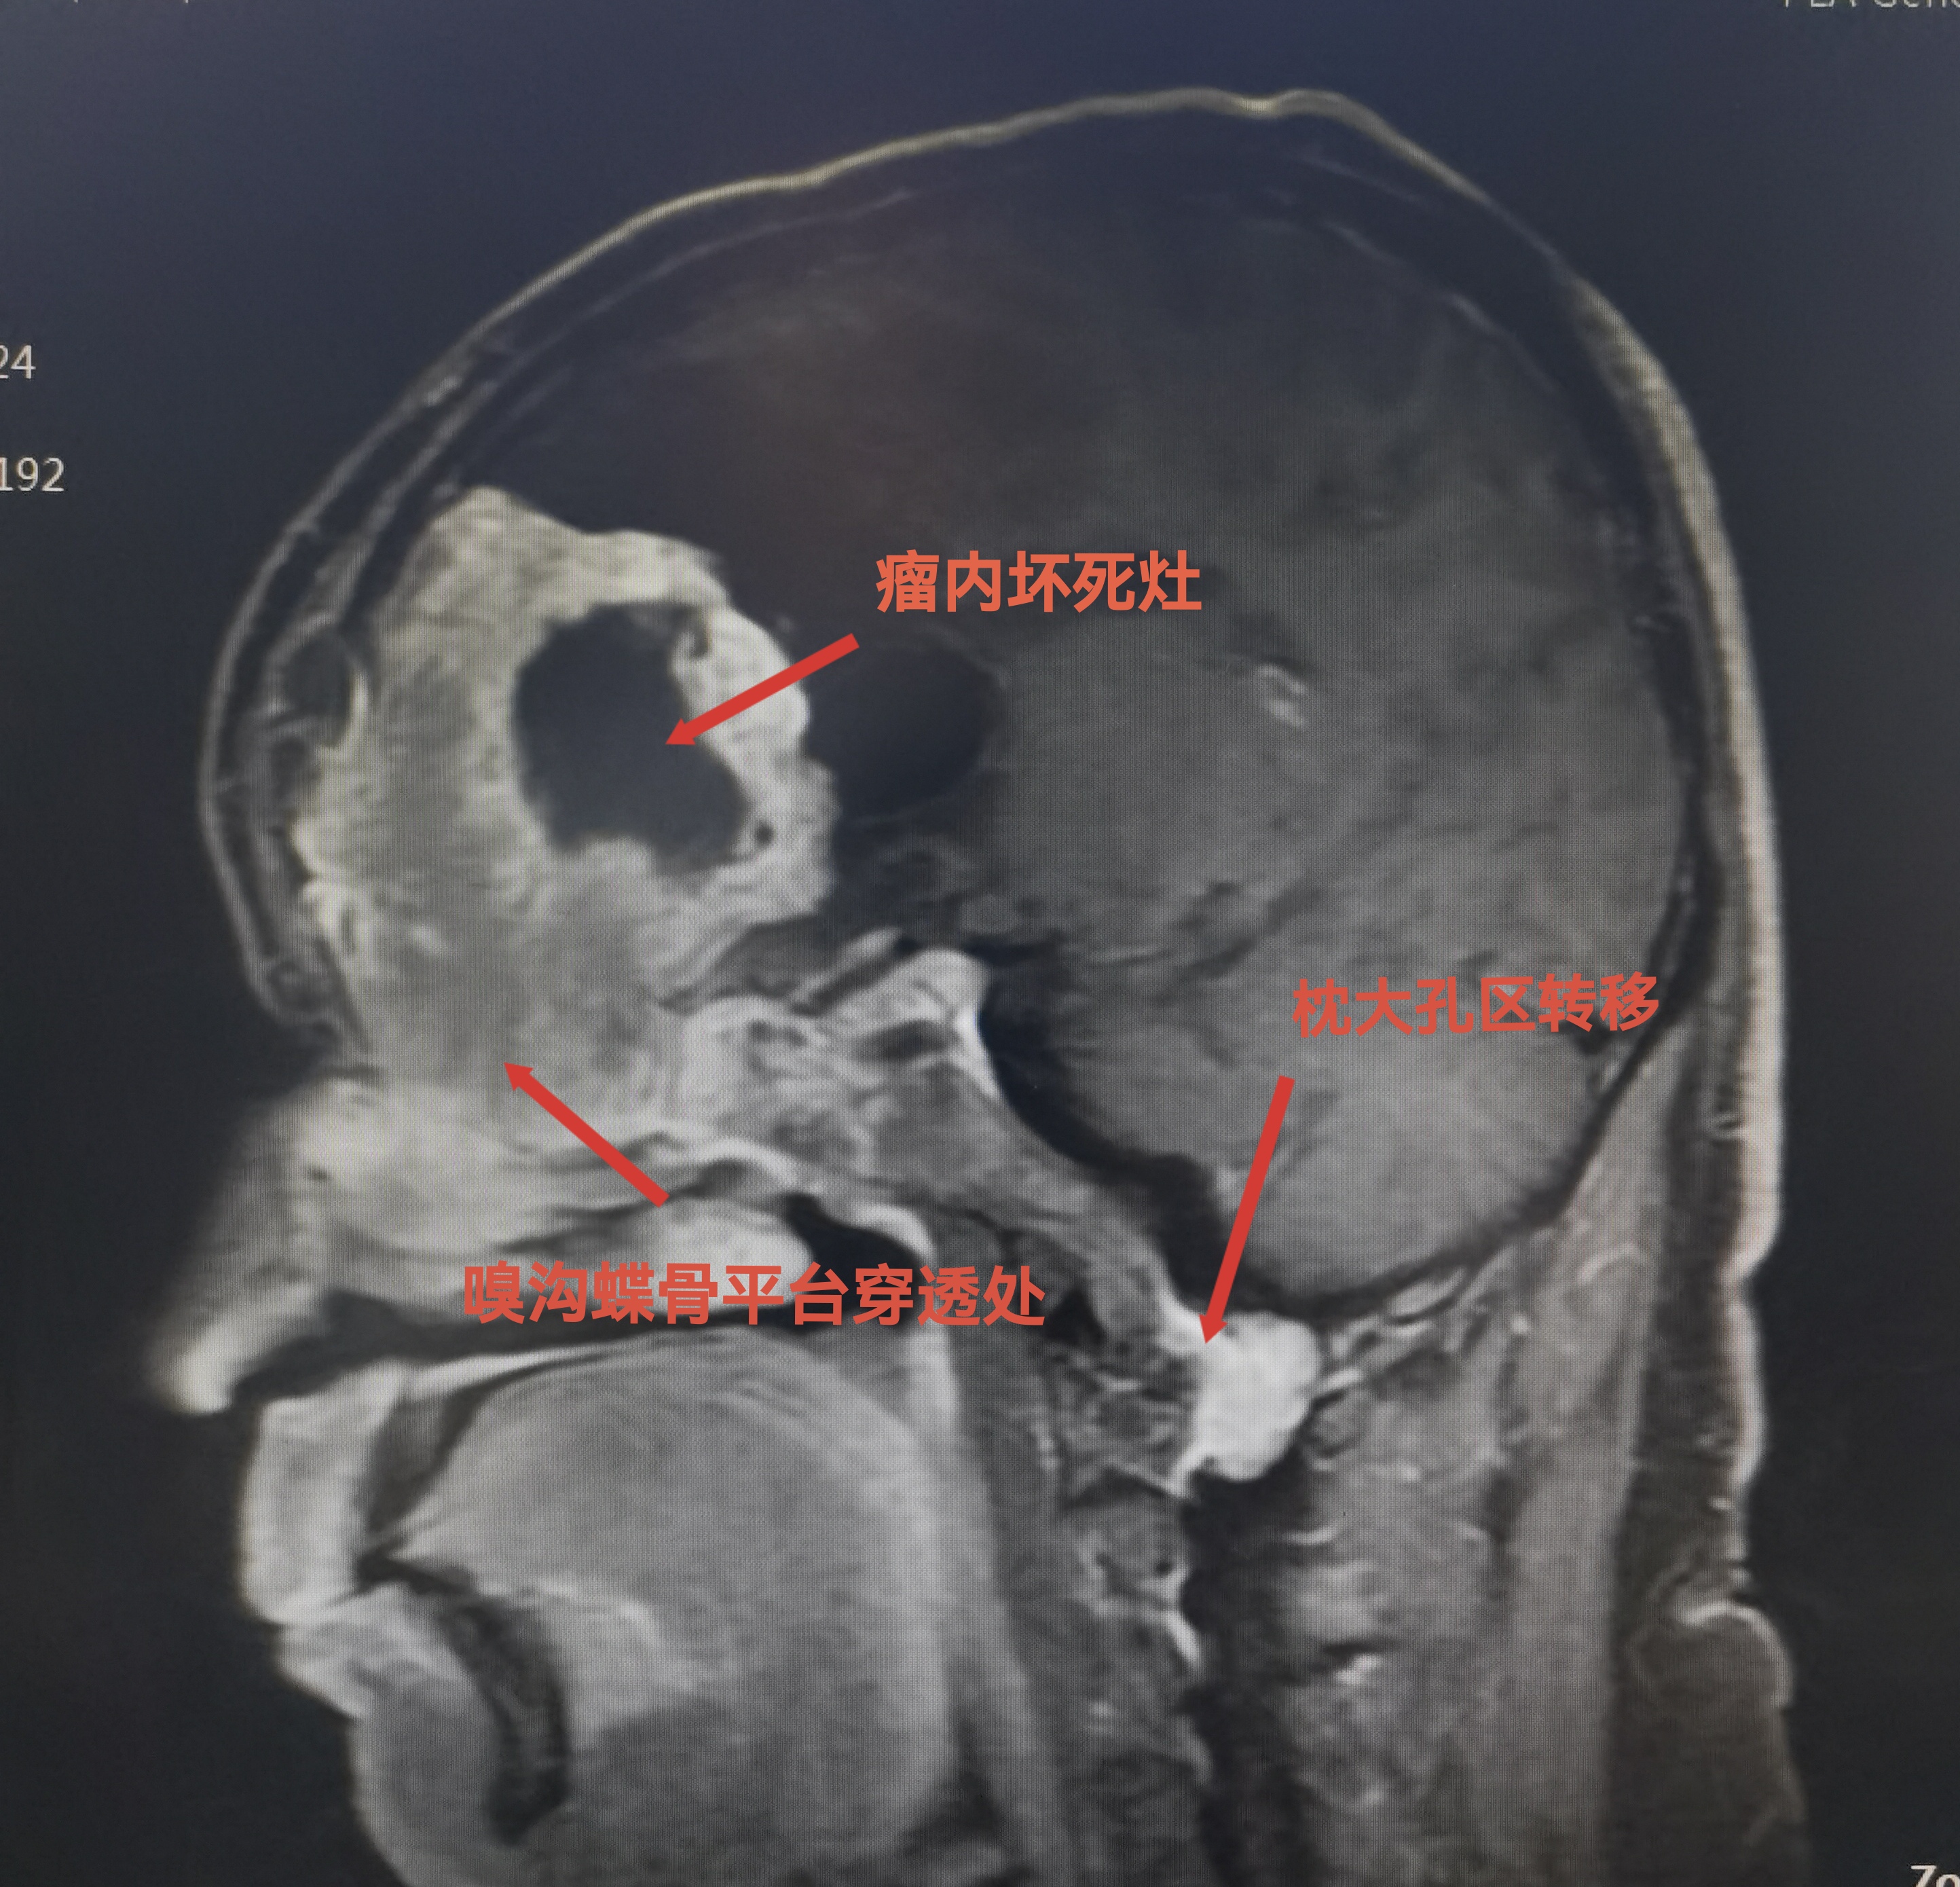

MRI可见肿瘤巨大,中鼻道以上,蝶窦筛窦及双侧额底均为肿瘤组织占据,向两侧到蝶骨嵴。肿瘤分叶状,可明显增强,核心区有坏死。后部可见粗大的静脉。双侧大脑前动脉位于肿瘤的后部。

枕大孔区种植转移,挤压脑干。已于6周前切除。

肿瘤向后到鞍结节前床突,向外到两侧的蝶骨嵴。